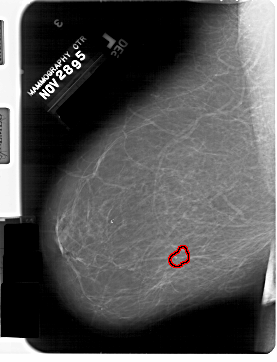

A_1332_1.LEFT_MLO

LEFT_MLO LINES 6871 PIXELS_PER_LINE 5251 BITS_PER_PIXEL 12 RESOLUTION 43.5 OVERLAY

FILE: A_1332_1.LEFT_MLO.OVERLAY

TOTAL_ABNORMALITIES 1

ABNORMALITY 1

LESION_TYPE CALCIFICATION TYPE PLEOMORPHIC DISTRIBUTION CLUSTERED

ASSESSMENT 4

SUBTLETY 2

PATHOLOGY BENIGN

TOTAL_OUTLINES 1

BOUNDARY